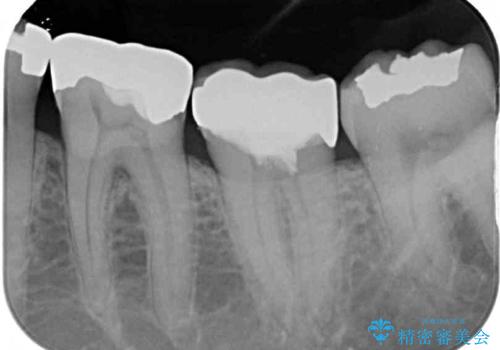

- 痛みを感じ近医を受診したものの、違和感が改善しないとのことで来院された患者様です。

診査をしたところ、神経組織に炎症及ぼすような大きなむし歯があることが分かりました。

虫歯が歯髄腔(神経の部屋)に達している可能性が非常に高かったため、炎症を起こしている神経組織を部分的に切除し、歯根部分の神経組織を保存する治療法が望ましいと考えられました。

歯質の欠損が大きいため、処置後はオールセラミッククラウンにて補綴治療を行うこととしました。

神経組織を部分的に除去することが分かっていたため、ラバーダムなどの環境を整え、無菌的環境下にて処置を進めて行きました。

虫歯は深くまで進行しており、歯冠部の神経から出血が認められました。神経を部分的に除去したところ出血が治まったので、生体親和性の非常に高いセメントにて充填し、仮封をしました。

後日状態を確認したところ、残された神経に異常は認められませんでした。